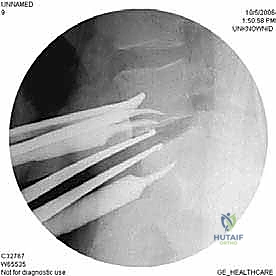

- الأشعة السينية الديناميكية (Dynamic X-rays): صور في وضعيات الانحناء للأمام والخلف لتقييم مدى عدم استقرار العمود الفقري (الانزلاق الفقري - Spondylolisthesis).

- التصوير المقطعي المحوسب (CT Scan): يقدم تفاصيل دقيقة للغاية عن البنية العظمية، وهو ضروري جداً للتخطيط الجراحي، خاصة في حالات استئصال الجسم الفقري أو وجود تعظم شديد.

خطوات إجراء جراحة ALIF بالتفصيل

تُجرى هذه العملية المعقدة تحت التخدير العام، وتتطلب مهارة فائقة وتنسيقاً دقيقاً.

الخطوة 1: الشق الجراحي والوصول

يقوم الجراح بإجراء شق صغير (عادة من 3 إلى 5 بوصات) في أسفل البطن. يتم إزاحة عضلات البطن بلطف جانباً دون قطعها (في الغالب).

الخطوة 2: التعامل مع الأوعية الدموية (Vascular Mobilization)

هذه هي الخطوة الأكثر دقة. أمام العمود الفقري القطني توجد الأوعية الدموية الكبرى في الجسم (الشريان الأورطي والوريد الأجوف السفلي وتفرعاتهما). باستخدام أدوات دقيقة ورؤية مكبرة، يتم تحريك هذه الأوعية بلطف شديد لحمايتها وكشف القرص الفقري المستهدف (غالباً L4-L5 أو L5-S1).

الخطوة 3: استئصال القرص (Discectomy)

بمجرد كشف القرص، يقوم الأستاذ الدكتور محمد هطيف بإزالة المادة الغضروفية التالفة بالكامل. يتم تنظيف الصفائح النهائية للفقرات (Endplates) العلوية والسفلية بعناية فائقة للوصول إلى العظم النازف، وهي خطوة حاسمة لضمان نمو العظم الجديد والتحامه.

الخطوة 4: التحضير وزراعة القفص (Implant Insertion)

يتم قياس الفراغ المتبقي بدقة لاختيار الحجم المثالي للقفص الجراحي (Cage). يُصنع هذا القفص عادة من مادة PEEK أو التيتانيوم، ويتم حشوه بمادة عظمية (طعم عظمي ذاتي من المريض، أو طعم صناعي، أو بروتينات محفزة لنمو العظم BMP). يتم إدخال القفص بقوة في الفراغ، مما يؤدي فوراً إلى استعادة ارتفاع القرص الطبيعي وتوسيع المخارج العصبية (تخفيف الضغط غير المباشر).

الخطوة 5: التثبيت (Fixation)

لضمان أقصى درجات الثبات والسماح للعظم بالاندماج بمرور الوقت، يتم تثبيت القفص باستخدام شريحة معدنية صغيرة ومسامير من التيتانيوم تُثبت في الأجسام الفقرية من الأمام. في بعض الحالات، قد يرى الدكتور هطيف ضرورة إضافة تثبيت خلفي بمسامير عبر الجلد (Percutaneous Pedicle Screws) لزيادة الدعم.

الخطوة 6: الإغلاق

بعد التأكد من وضعية الغرسات باستخدام الأشعة السينية داخل غرفة العمليات، يتم إعادة الأوعية الدموية والأعضاء الداخلية إلى وضعها الطبيعي، وتُغلق طبقات البطن بخيوط تجميلية.